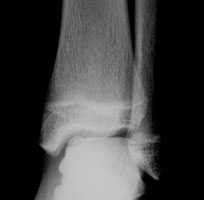

Не смотря на то, что Loomer с соавт. сообщили, что только от 50% до 66% остеохондральных дефектов обнаруживаются при помощи обычной рентгенографии, данный метод является важной отправной точкой и может быть полезен для исключения другой патологии голеностопного сустава [20]. Рентгенологическое исследование голеностопного сустава должно включать переднюю, заднюю и в 3⁄4 внутренней ротации проекции. Все проекции выполняются стоя (под нагрузкой) и называются функциональными. Функциональные рентгенограммы могут быть полезны для выявления сопутствующей нестабильности голеностопного сустава, проекция 3⁄4 во внутренней ротации, помогает в визуализации щели межберцового синдесмоза, а так же отображает передне-внутрений импижмент (таранной и большеберцовой кости) в случае его наличия. Выполненные в положении подошвенного сгибания прямая и 3⁄4 проекция во внутренней ротации могут быть полезны в выявлении заднемедиального поражения таранной кости. Рентгенологические признаки, которые могут быть определены, варьируются от небольших участков сдавления субхондральной кости до крупных отслоенных остеохондральных фрагментов. Радиографическая

На КТ определяется остеохондральное повреждение таранной кости.

Рентгенография

Рутинное рентгенологическое исследование включает рентгенографию обоих голеностопных суставов в прямой и боковой проекциях. На рентгенограммах можно увидеть отслоенный костный фрагмент. Изначально, на начальных стадиях болезни, площадь повреждения может быть очень мала, в связи с чем она не будет видна на рентгенограммах. Иногда изменения становятся видны только при рентгенологическом исследовании в динамике.